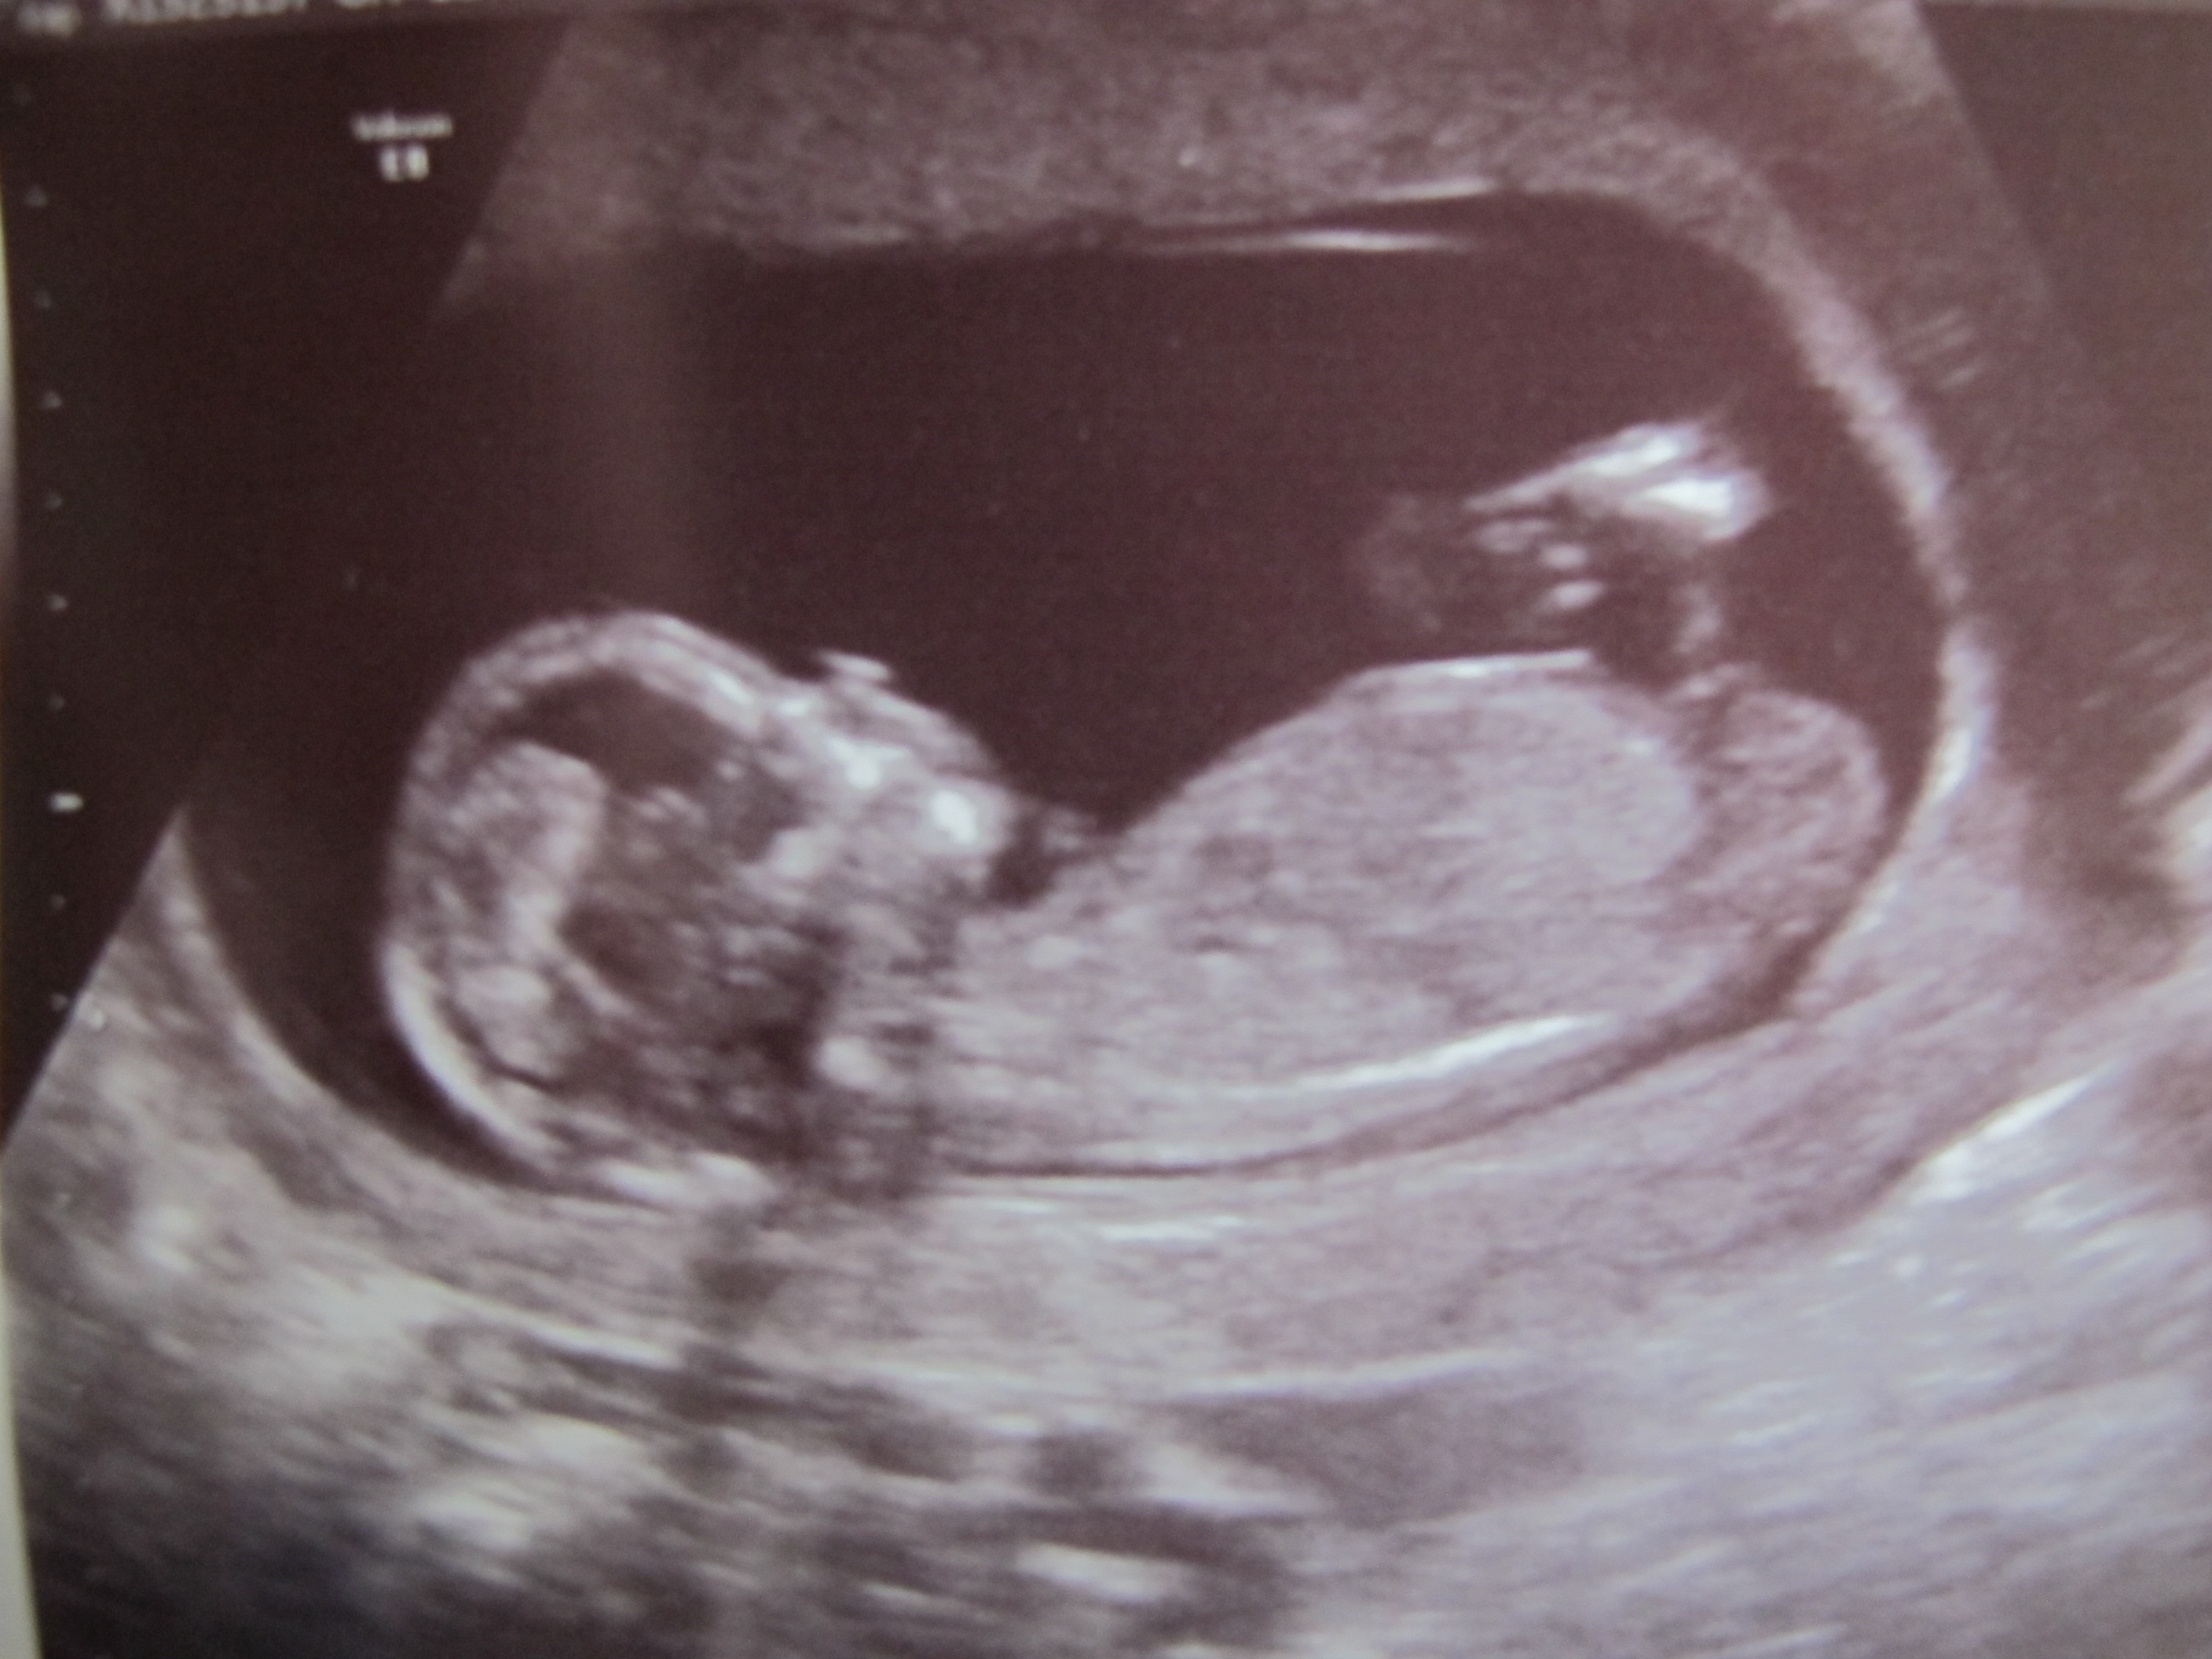

pics from 12 week scan this morning, baby dated at 13+1 weeks. Any ideas? sure I saw a boy nub but now looking at the pics I'm not so sure....still have a bit of hope that this is a girl, am I totally wrong?Attachment 1287Attachment 1288Attachment 1289